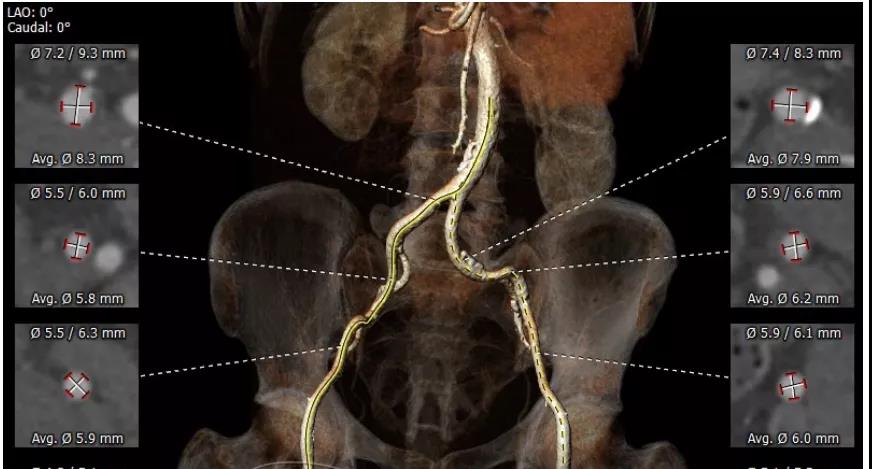

CT重建显示患者双侧髂动脉、股动脉、锁骨下动脉质量极差,多发钙化狭窄伴局部夹层,无法经股动脉和锁骨下动脉入路。而且患者重度肺气肿致心脏两侧受压,心尖被压缩在胸骨及肋弓骨性融合后方,亦无法经心尖入路。评估双侧颈动脉近端均有钙化斑块伴轻度狭窄,平均管径约6mm,左侧管径略大于右侧。颅内Willis环交通支通畅,可以耐受经单侧颈动脉介入手术。

颈动脉评估